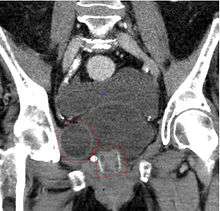

CT scan (coronal reconstruction) showing an artificial urethral sphincter in a woman

In rare cases, a surgeon implants an artificial urinary sphincter,[21] a doughnut-shaped sac that circles the urethra. A fluid fills and expands the sac, which squeezes the urethra closed. By pressing a valve implanted under the skin, the artificial sphincter can be deflated. This removes pressure from the urethra, allowing urine from the bladder to pass.